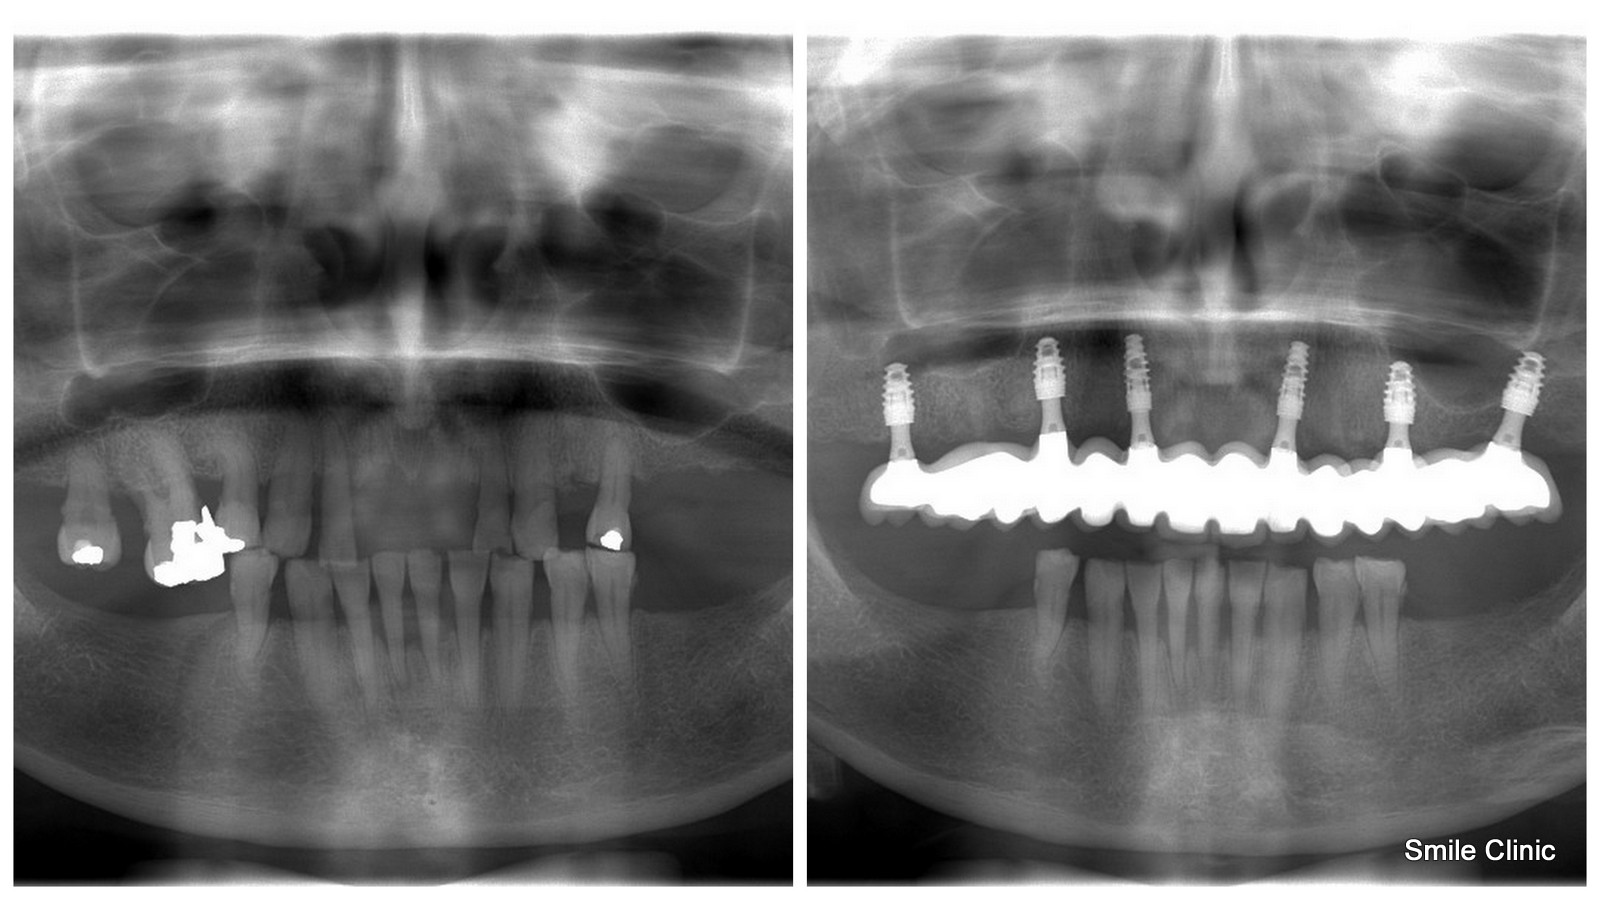

A month later Irene came to visit us for her 1st treatment session along with her husband which involved the extractions of the few remaining upper teeth, placing 6 dental implants and fitting a temporary bridge to have during the healing time.

A few months later Irene completed her dental treatment by having 14 dental crowns placed across the 6 dental implants as a bridge and as you can see here from the photographs, the result is fantastic!